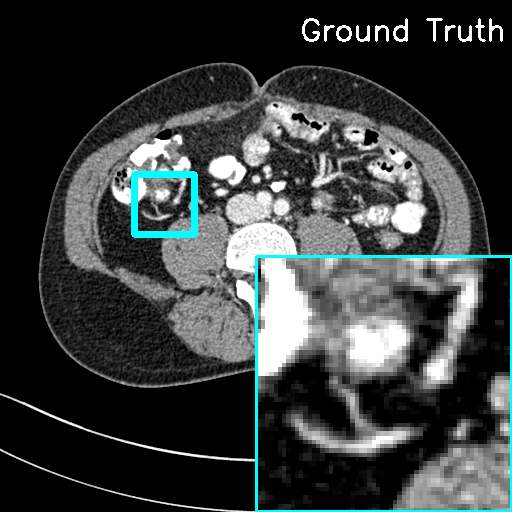

We assess the reconstruction performance of LInFBP under quarter-view cases, i.e., only quarter-view and quarter-view with quarter-dose conditions. Fig. 4 and Fig. 5 present the reconstructed CT images using Li FBP-R, Li FBP-H and our methods at quarter-view cases and quarter-view with quarter-dose cases, respectively. It can be observed from the visualizations that the proposed methods yield better results closer to the ground-truth with higher PSNR scores at all the cases, as indicated by the red circles and arrows in the error maps, compared to Linear FBP methods. Specifically, in Fig. 5, both F-LInFBP and L-LInFBP can reconstruct highly accurate structure textures with negligible artifacts compared to the ground-truth. The improvements in image quality can be ascribed to the accurate radon transform interpolation obtained by the LInFBP, which implies its effectiveness in low-dose CT imaging applications while maintaining image quality. It should also be noted that the L-LInFBP produces almost similar reconstruction performance with F-LInFBP, as seen in the least absolute errors compared to the ground-truth. This indicates that the linear basis functions in L-LInFBP can already represent the continuous backprojection in satisfactory accuracy while with evidently less complexity as compared to F-LInFBP.

For quantitative evaluation, Table 2 presents the quantitative measurements of the CT images reconstructed by the FBP algorithms with different interpolation strategies and the F-LInFBP and L-LInFBP methods at only quarter-view and quarter-view with quarter-dose conditions, respectively. It is seen that both the proposed F-LInFBP and L-LInFBP consistently achieve higher PSNR scores, lower NMSE scores, and higher FSIM scores for all the quarter-view cases and quarter-view with quarter-dose cases compared to other competing methods. And the L-LInFBP can obtain similar quantitative measurements with the F-LInFBP, which is consistent with the visual inspection.